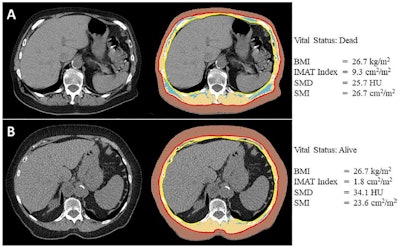

Body composition analysis of axial CT images at the level of the 12th thoracic vertebral body for two female patients ages (A) 74 and (B) 82 who underwent lobectomy for stage IIB non-small cell lung cancer, both with a body mass index (BMI, calculated as weight in kilograms divided by height in meters squared) of 26.7. The former patient (A) died 2 years after surgery, and the latter patient (B) was censored after 5.2 years. The segmentation results on the right show skeletal muscle (beige), subcutaneous adipose tissue (brown), and intermuscular adipose tissue (IMAT, blue). The anatomic fascia separating the body composition compartments are depicted in red (membranous layer of the superficial fascia) and yellow (fascia transversalis and endothoracic fascia of the fascia trunci interna). Images and caption courtesy of the RSNA.

Using CT imaging, the authors assessed at patients' 12th thoracic vertebral level the indexes and densities of skeletal muscle, subcutaneous adipose tissue, and intermuscular adipose tissue. Of the total patient cohort, 219 (26%) died after a median follow-up of 5.3 years.

- Increased myosteatosis, represented by a decreased skeletal muscle density and increased intermuscular adipose tissue index, was associated with worse overall survival (adjusted hazard ratio, 0.87, or p < 0.001 for skeletal muscle density and 1.24, or p < 0.001 for intermuscular adipose tissue).